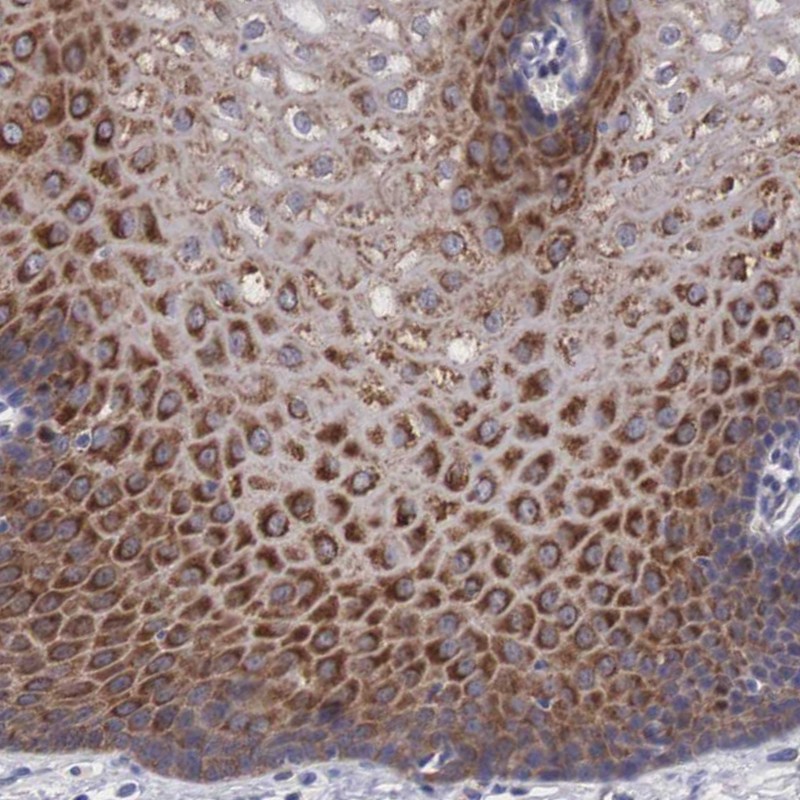

Immunohistochemical staining of human esophagus shows strong cytoplasmic positivity in squamous epithelial cells.